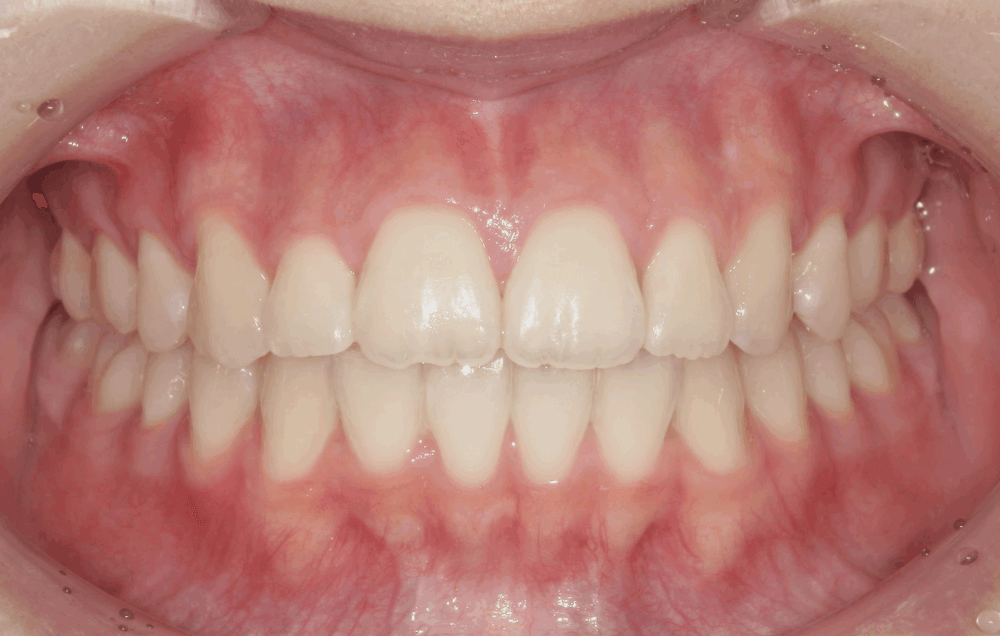

まとめ・治療後の変化

治療後の写真では、歯並びのガタつきが整い、前歯の角度も自然に改善されています。

Eラインに対してもバランスが取れ、力を入れなくても唇を閉じられる、リラックスした口元になりました。

「口元の力みがなくなって、表情が自然になった」と患者様にも喜んでいただけました。今回のような出っ歯や叢生のケースでは、“どれだけ引っ込めるか”だけではなく、“口元の自然さをどう保つか”がとても大切です。

同じ「出っ歯の改善」でも、骨格や筋肉のバランスを考慮することで仕上がりが大きく変わります。

治療前後の比較

治療前

治療後(15か月)